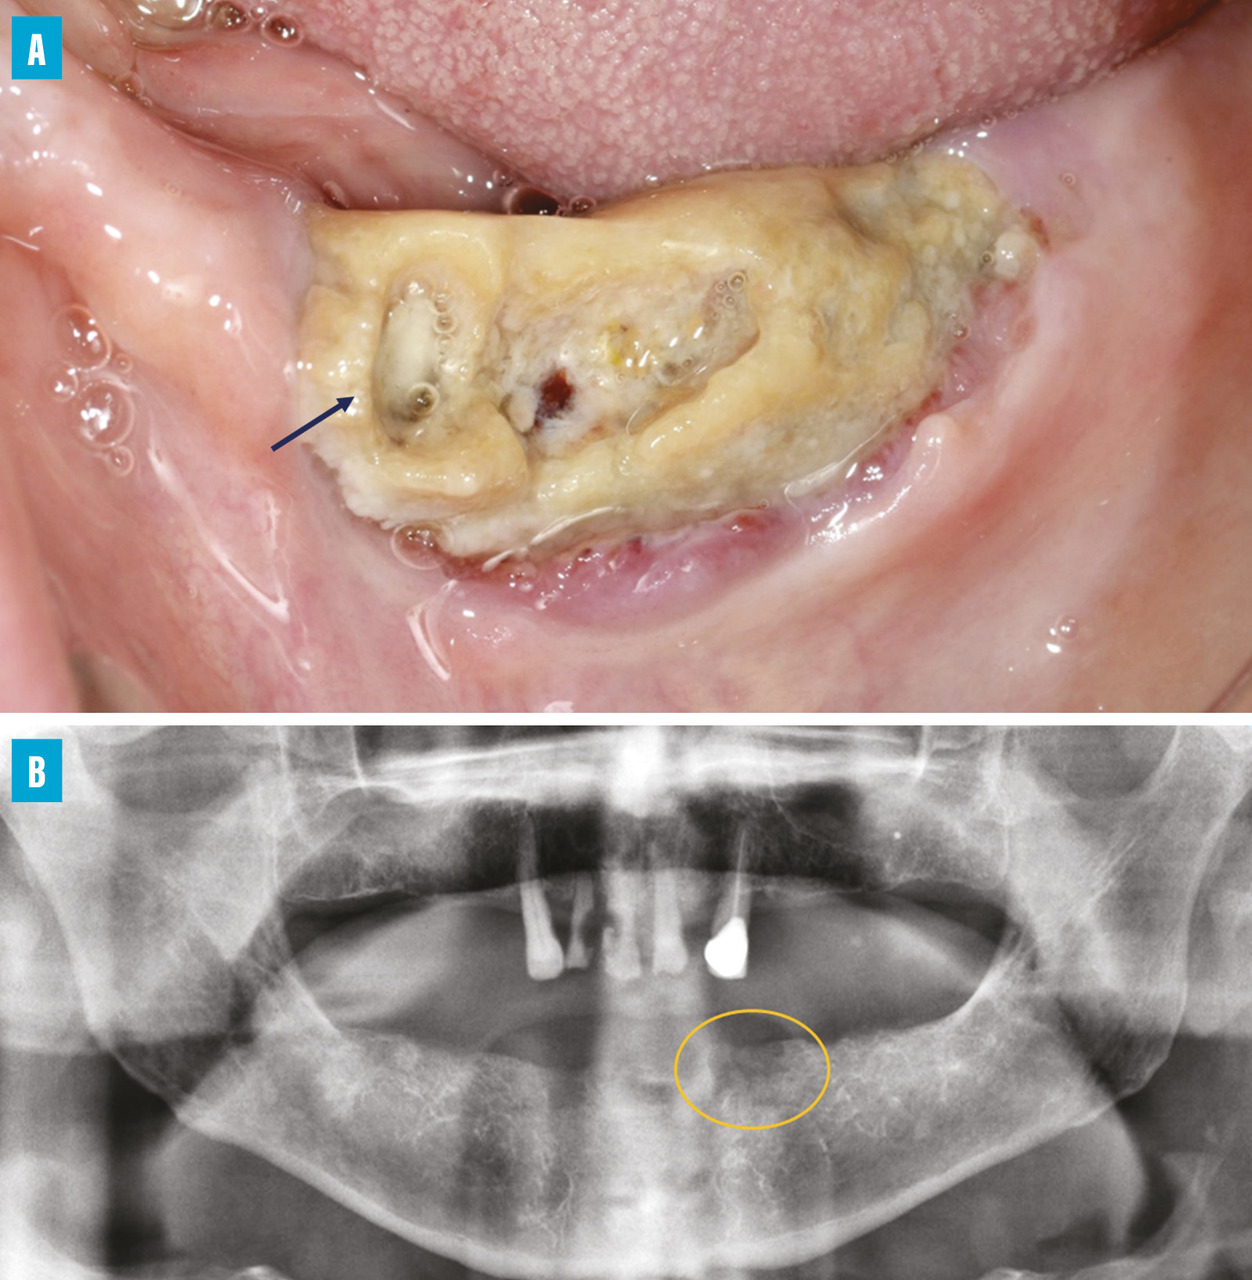

Ostéonécrose de stade 2 au niveau du site extractionnel de la canine mandibulaire gauche chez une patiente ayant reçu un traitement sous-cutané par dénosumab, dans un contexte de cancer du sein avec métastases osseuses.

A. Vue intra-orale de l’arcade mandibulaire montrant l’exposition de l’os alvéolaire au niveau du site de la canine gauche ;